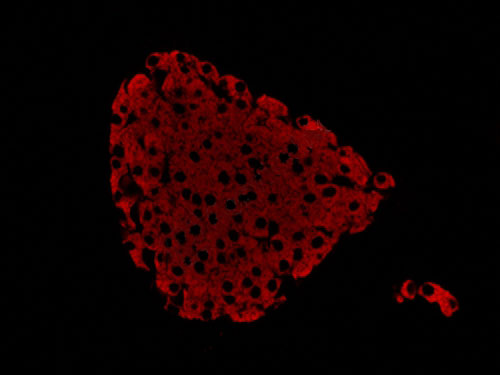

熒光顯微鏡是免疫熒光的基本工具。它是由光源、濾板系統和光學系統等主要部件組成。是利用一定波長的光激發標本發射熒光,通過物鏡和目鏡系統放大以觀察標本的熒光圖像。

正置顯微鏡型號:NIKON Eclipse ci;軟件:NIS_F_Ver43000_64bit_E;成像系統:NIKON digital sight DS-FI2。可選擇100×、200×和400×不同放大倍數。共配置紅、綠、藍三個通道:DAPI(EX激發340-380,BA發射435-485);FITC(EX激發465-495,BA發射515-555);G-2A(EX激發510-560,BA發射590)

實驗結果展示:

(3)實驗結果:圖片×6,每張圖片包括merge圖,單通道圖(常規選擇同視野下200×3、400×3)